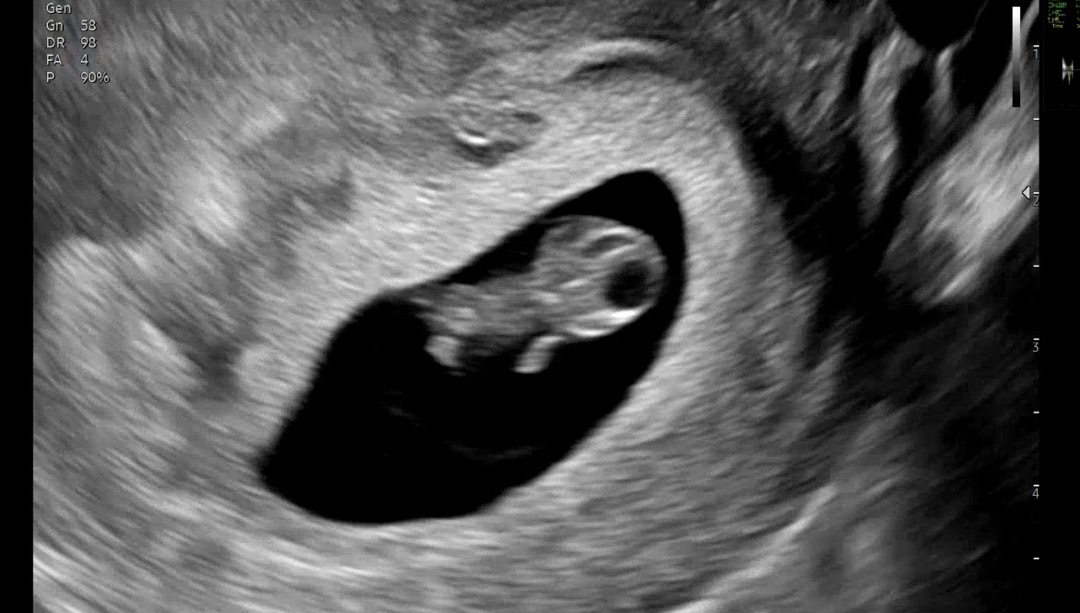

심장소리도 좋고 아주 잘 크고 있다고 해요 1.7 cm 이고 너무 귀엽죠? 젤리곰초음파 같은가여? ㅎㅎ 입덧이 정말 1도 없어서 오히려 무슨 문제가 잇는거 아닌가 걱정햇어요